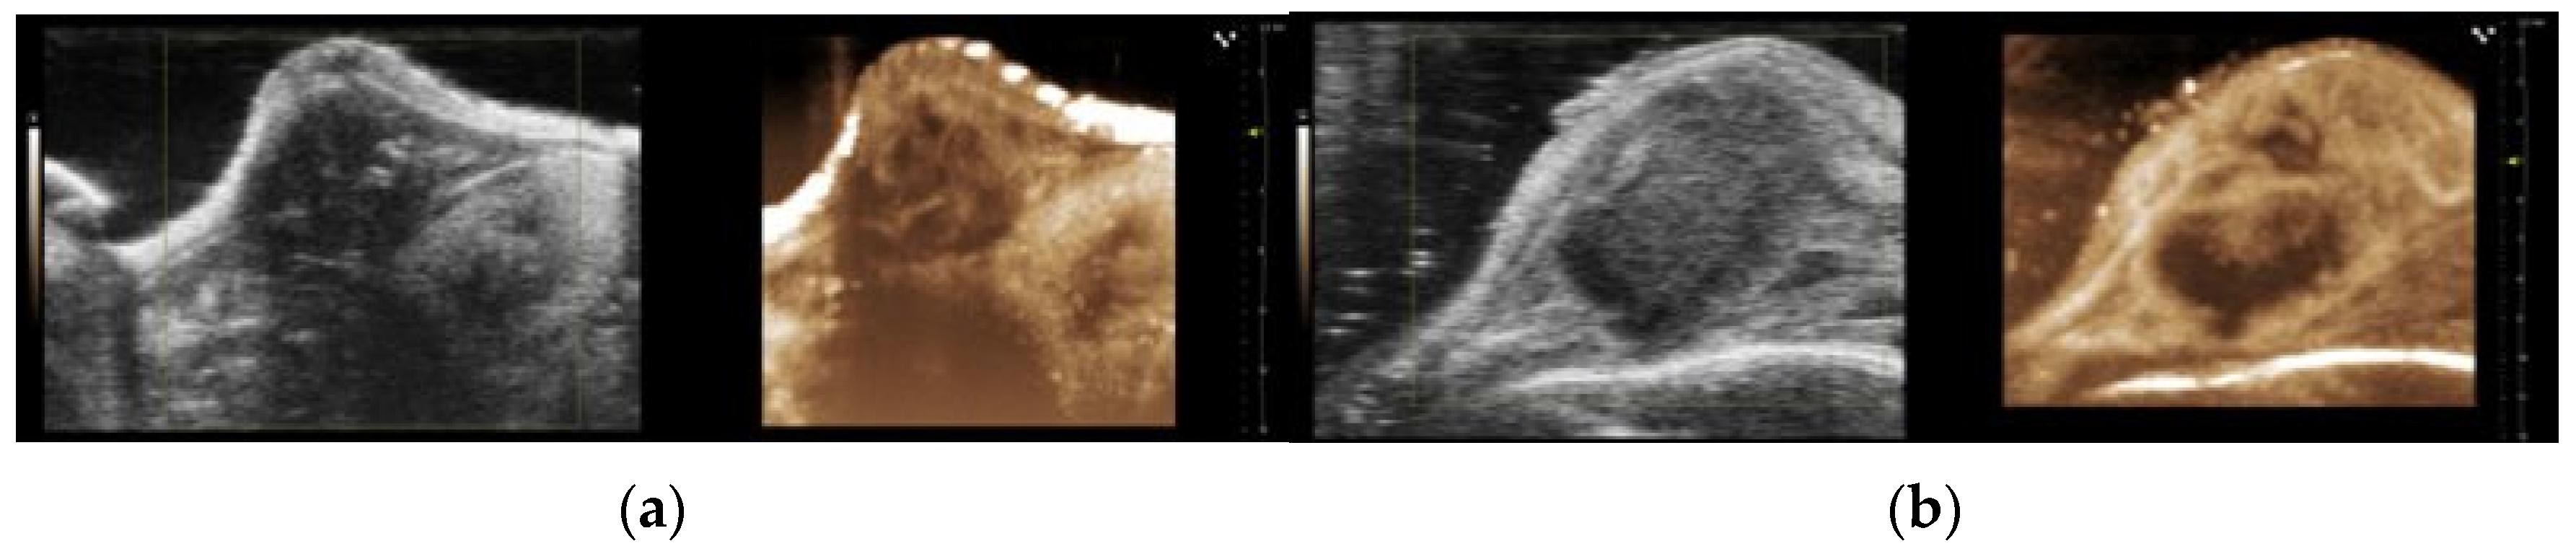

The B-mode ultrasound images and the maximum intensity projection (MIP) of the nonlinear contrast mode images of the orthotopic and subcutaneous tumours are presented in Figure 8a,b, respectively. A qualitative assessment of the images indicated that there were large dark regions with no signal from the contrast agent in the subcutaneous tumours, which were consistent with the larger necrotic area observed in the HES and MT sections (Figure 1d).

Figure 8. Representative B-mode and maximum intensity projections (MIP) based on the nonlinear contrast mode images for the orthotopic tumours (a) and the subcutaneous tumours (b).

The microenvironment differed between the orthotopic and subcutaneous tumours, and the type of necrosis was one of the main differences. The orthotopic tumours presented focal necrotic regions, while the subcutaneous tumours had large infarct-like necrotic areas. The MIP images of the subcutaneous tumours also demonstrated larger dark regions with no contrast agent, indicating necrotic areas. This was consistent with the large necrotic regions observed in the histological assessment, as seen in the other subcutaneous PDAC models [32]. The difference in the number of functional vessels and the perfusion might explain the difference in necrosis. Although the CEUS data indicated that the subcutaneous tumours were overall better vascularised than the orthotopic tumours, the lower number of functional vessels imaged by the CLSM might suggest that parts of the tumours had fewer blood vessels, causing larger necrosis. It is essential to add that the CLSM data was based on the microvasculature from a limited number of images of one to two sections from each tumour. Therefore, it was a limited estimation of the fraction of functional vessels in the whole tumour volume. It should also be mentioned that the difference between the orthotopic and subcutaneous tumours regarding the functional vasculature was not statistically significant. The CEUS perfusion analysis was based on a significantly thicker cross-section of the tumour. A notable difference between the CLSM of the functional vessels and the CEUS estimation of the vascular parameters was the spatial resolution, and thus possibly the kind of vessels that were analysed.